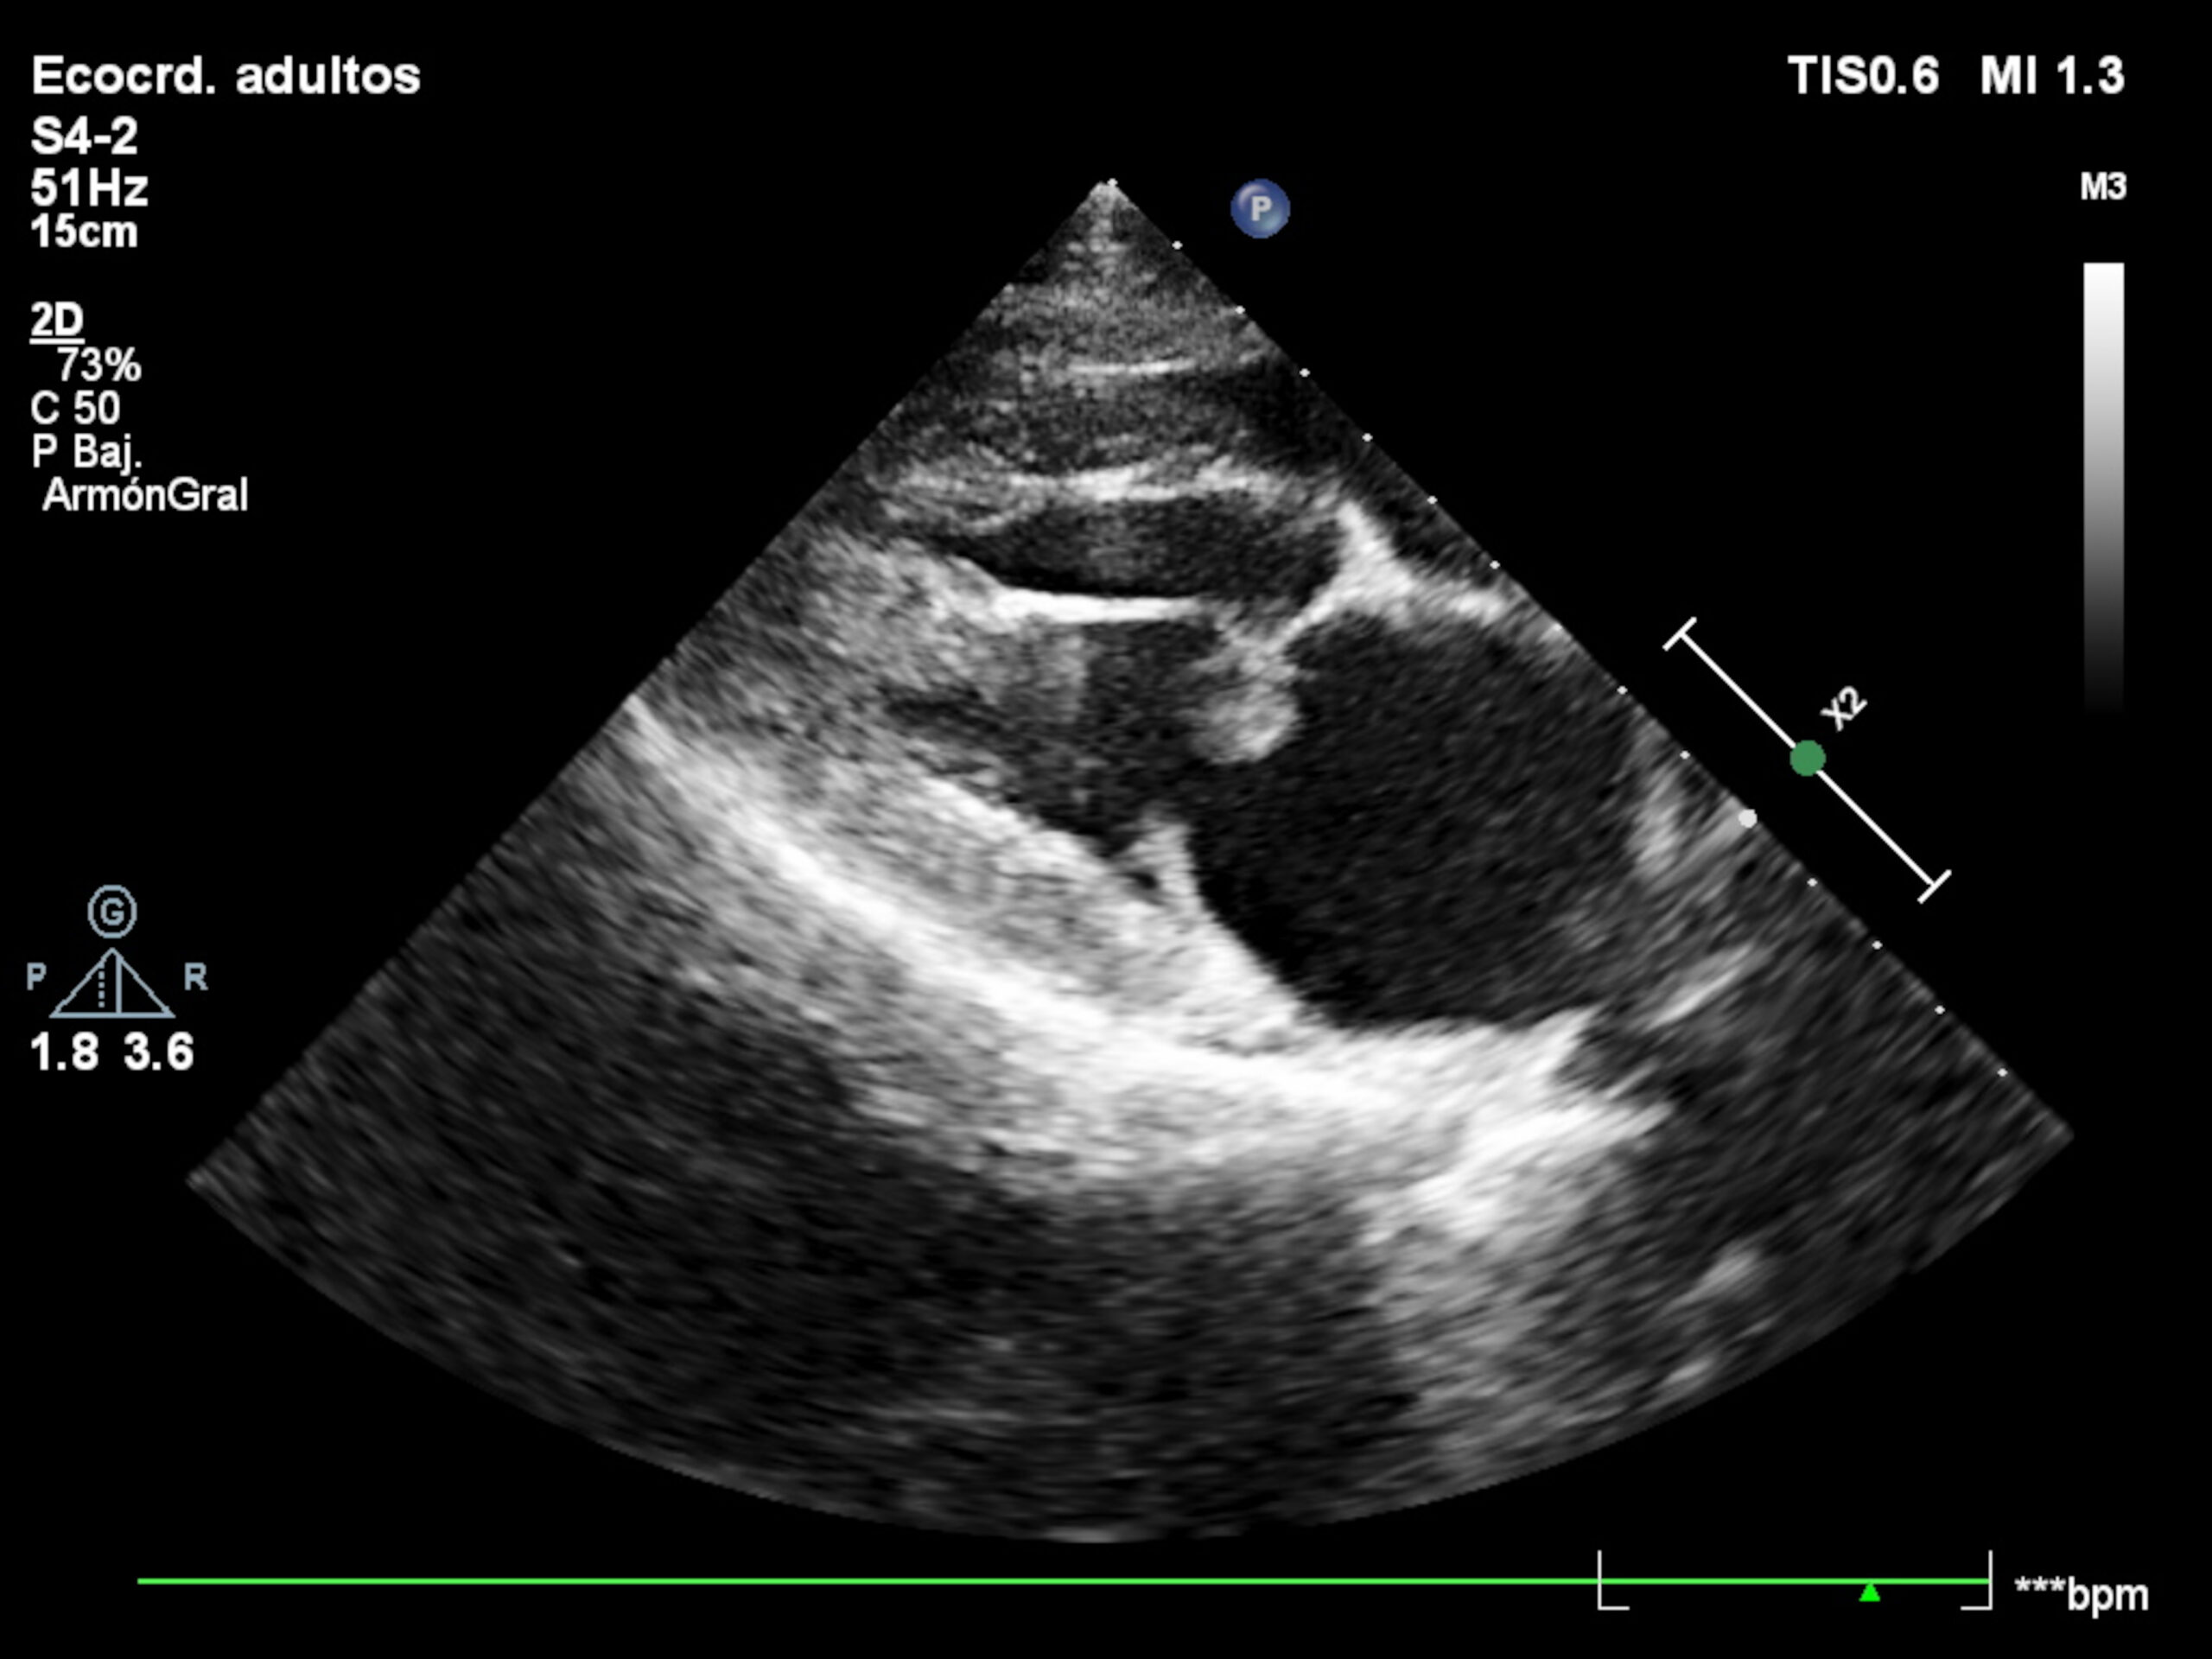

Mastín del Pirineo, macho castrado de 5 años, que acude por marcada debilidad generalizada, disuria y hematuria. En consulta se detectan mucosas congestivas, taquicardia de 180 latidos por minuto con ritmo irregular y fiebre de 40,3 °C. El electrocardiograma revela una arritmia ventricular multifocal. En el sedimento urinario se visualiza la presencia de piuria y bacteriuria con cocos intracelulares. Ante la sospecha de una urosepsis, se cursa un cultivo de orina y un hemocultivo (Tablas 1 y 2). Se realiza una ecocardiografía en la que se observa un engrosamiento marcado de la válvula mitral junto con la presencia de vegetaciones (Figura 3).

Figura 3. Imagen ecocardiográfica donde se observa un engrosamiento marcado de la válvula mitral junto con la presencia de vegetaciones.